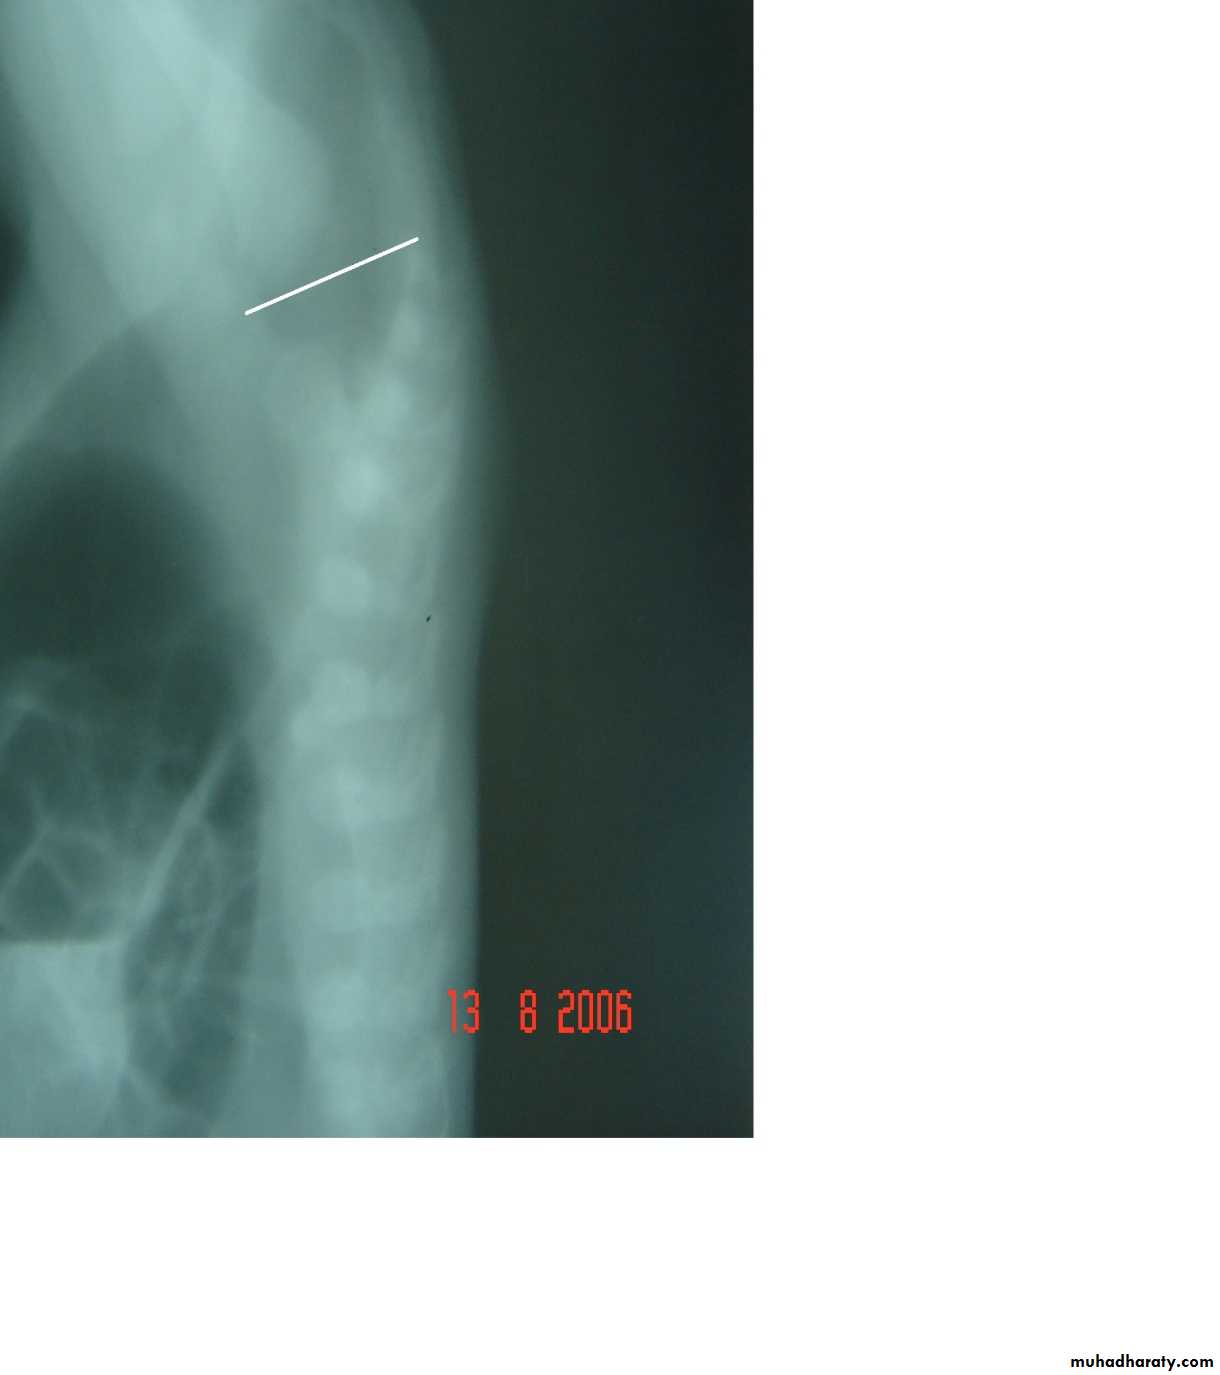

Anorectal Anomalies

First and second photos:

Lateral invertogrampubococcygeal line

It is low type

Third photo:

Lateral decubitus x-ray

Low type

Anal dimplePass of meconium through the urethra

High typeSubcutaneous meconium – cutaneous fistula – low type